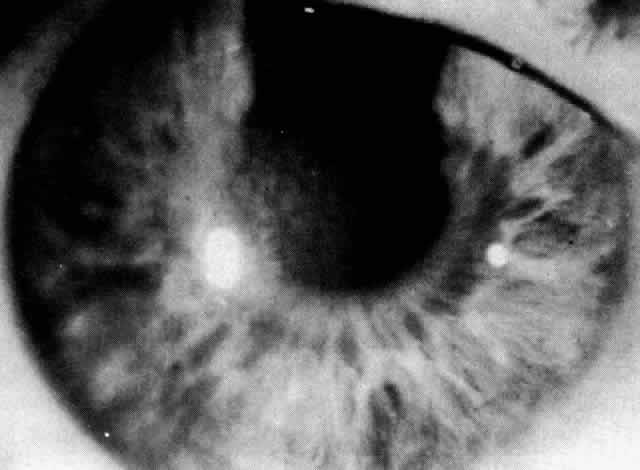

The literature contains many descriptions and names for posterior polymorphous dystrophy owing to the variety of clinical findings.189–193 Koeppe is credited with the first description in 1916 of six patients with congenital pits on the posterior surface of the cornea. Subsequently, multiple clinical and histopathologic reports described this generally bilateral, asymmetric, or even unilateral dystrophy. Although vesicles (Fig. 12) at the level of Descemet's membrane are traditionally described, clinical examination reveals a variety of opacifications of the posterior corneal layers.192

Fig. 12. Posterior polymorphous dystrophy: posterior corneal vesicles.